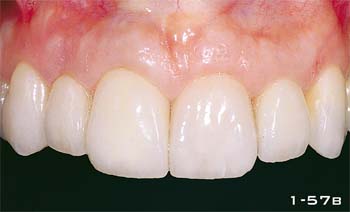

Abb. 1-57b Nahaufnahme zehn Tage nach dem Einsetzen der definitiven Versorgung.

Abb. 1-57c und 1-57d Nahaufnahme des Lächelns vor und nach der Behandlung.

Abb. 1-57e Nahaufnahme der definitiven Versorgung.